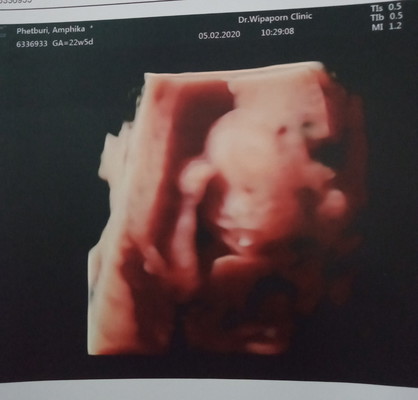

ท้อง 23 Week แม่ๆ บ้านไหนน้ำคร่ำน้อยบ้างค่ะ อันตรายต่อน้องในท้องมั้ยค่ะ คุณหมอแนะนำไห้ดื่มน้ำเยอะๆ แม่ๆมีวิธีอื่นแนะนำมั้ยค่ะ แนะนำหน่อยค่ะ ขอบคุนค่ะ